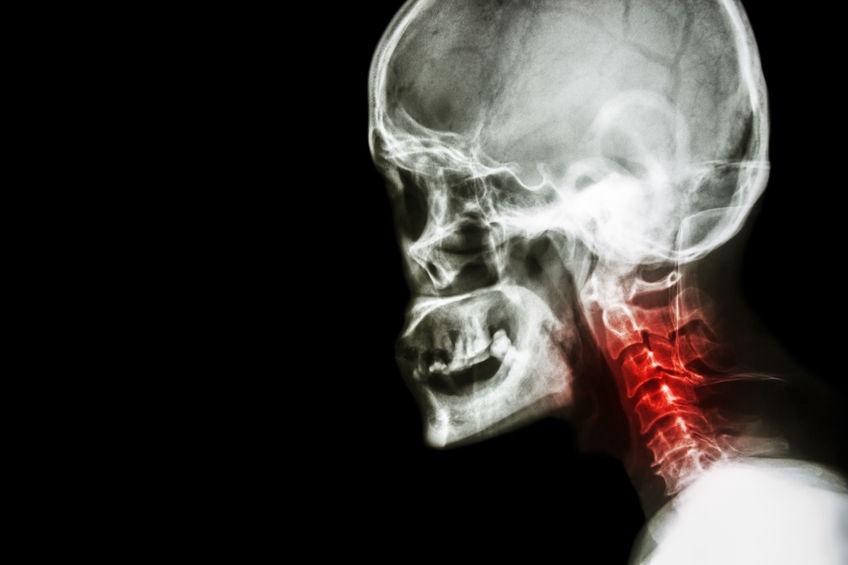

颈椎病是属于临床的常见病,多发病。近几年由于人们长时间玩手机的习惯,颈椎病的发病率呈逐年上升趋势,严重者可影响患者的工作生活和学习。

颈椎病主要是颈椎骨关节炎,增生性颈椎炎和颈神经综合症,颈椎间盘脱出症的总称。是一种以退行性病变为基础的疾患。主要是由于颈椎的长期劳累,骨质增生,或者是椎间盘脱出,韧带增厚,导致颈椎脊髓交感神经或者是椎动脉受压,出现一系列功能障碍的临床综合征。

颈椎病的临床表现主要是:脊椎出现疼痛,上肢无力,手指发麻,下肢乏力,行走困难,头晕,恶心呕吐,甚至视物模糊等情况。

颈椎病根据其证型的不同,其临床表现也有些不一样,其中神经根型颈椎病,主要的表现是根性症状,如麻木疼痛,且范围与颈椎神经所支配的区域一致。脊椎型颈椎病主要的临床表现是颈脊髓损害的表现,一般通过ct可以确诊。椎动脉型颈椎病表现为间断性发作的眩晕,活动颈椎后一般可以缓解。颈型颈椎病也称局限性颈椎病,是指头,颈,肩臂疼痛及相应的压痛点,在x线片没有椎间隙狭窄等明显的退行性病变,但可以有颈椎生理曲度的改变,如颈椎曲度变直等。

图片来源:123RF